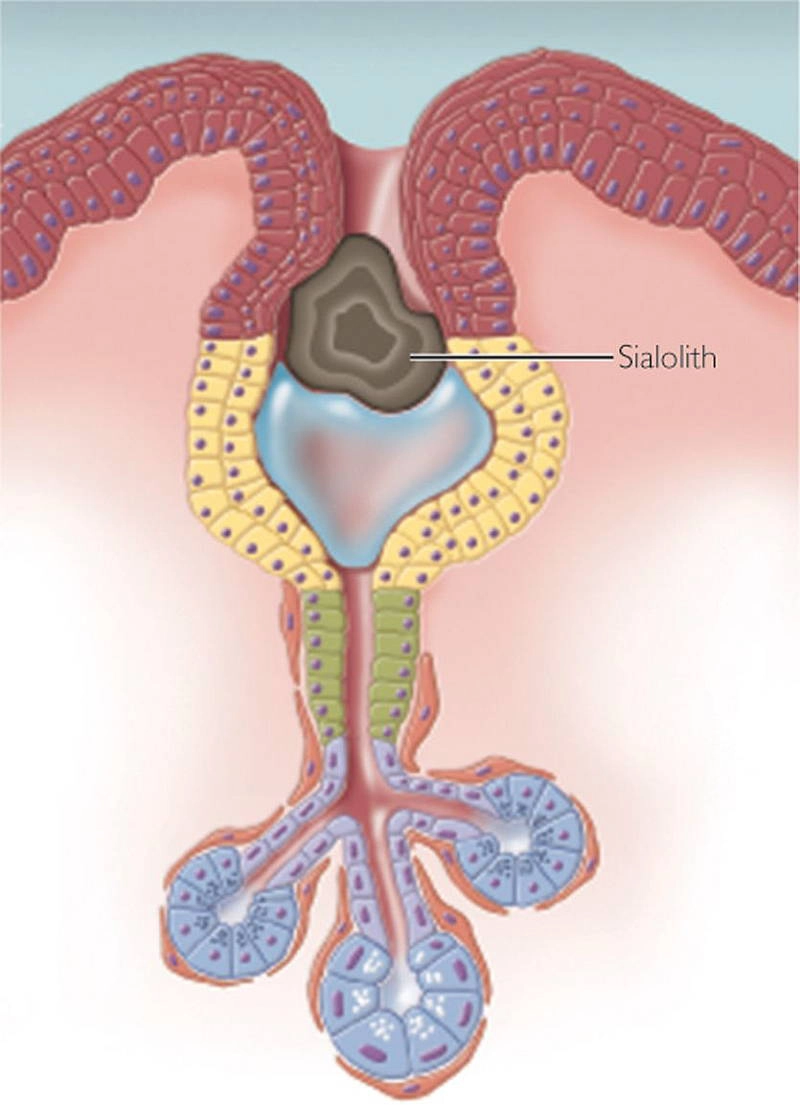

Sỏi tuyến nước bọt (Sialolithiasis)